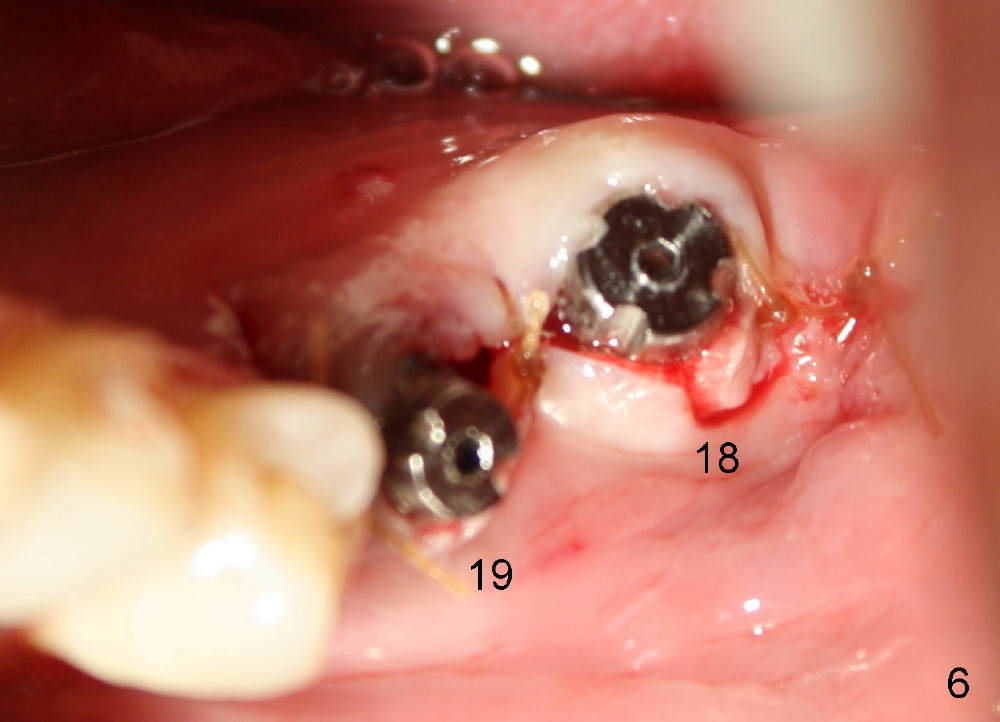

A 45-year-old man is a smoker (half pack a day). He returns for perio maintenance every 3 months. The teeth #18 and 19 have been extracted for long with supraeruption of #14 and 15 (Fig.1 arrows). CT confirms sufficient bone height (Fig.2) and width (Fig.3). Bone density is type II, as shown by CT and drilling. Relatively short implants are placed as deep as possible considering supraeruption of the opposing teeth (Fig.4 (4.5x14 and 5x14 mm taps at sites of #19 and 18, respectively) and Fig.5 (5x14 mm and 6x14 mm gingiva-level implants (I)). In order to avoid damaging the submandibular fossa, the implant at the site of #18 is tilted lingually (Fig.6). When short abutments (3 mm in height) are placed, there is enough clearance to place perio dressing. The abutment at the site of #18 becomes prematurely loose. It has to be removed 4 days postop. There is no sign of infection. Perio dressing is removed by the patient 7 days postop. He returns to clinic 8 days postop (Fig.7) for the remaining abutment to be removed. The wound appears to be healing normally.